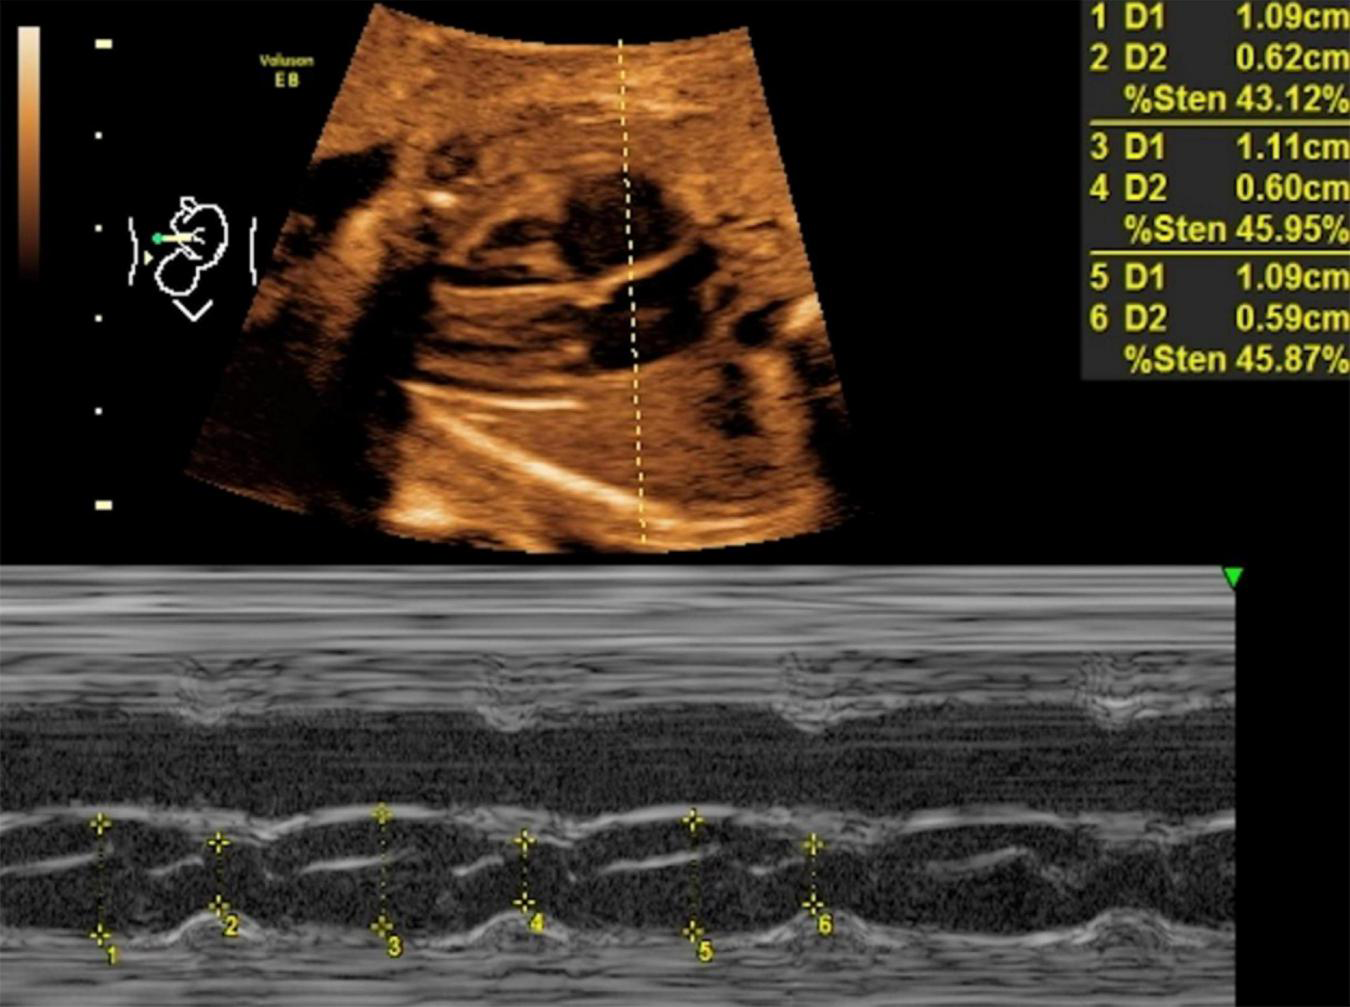

Mitral valve E/A ratio and tricuspid valve E/A ratio were not significantly different between the two groups (P > 0.05). GDM group showed significantly thicker IVSd (P < 0.001), higher DV-PI (P < 0.05), and significantly lower LASF than those in the control group (P < 0.001) (Figures 1, 2 and Table 2).

FIGURE 2

LASF in control fetuses at gestational age 26 weeks + 3 days. LASF, left atrial shortening fraction.

All women with gestational age of 24th–28th weeks underwent echocardiography. According to the echocardiography guidelines of American Society of Echocardiography (ASE) (9), pregnant women were placed in the supine position, and blood flow velocity of atrioventricular valve in early diastole (E peak) and late diastole (A peak) was measured to calculate E/A ratio. The blood flow spectrum in the ductus venous was acquired at the entrance of DV on the coronal section of the epigastrium. Ductus venosus pulsatility index (DV-PI) value was automatically recorded with a high-quality DV spectrum image acquired continuously within 3–5 cardiac cycles. IVS thickness at end-diastolic (IVSd) was recorded with M-mode in the long axis view. Then, the M-mode sampling line was moved to the left atrium, kept away from oval foremen, and the left atrial diameter at end-systolic (LAIDs) and end-diastolic (LAIDd) were measured successively, followed by LASF = (LAIDs-LAIDd)/LAIDs. All parameters were measured three times and averaged.